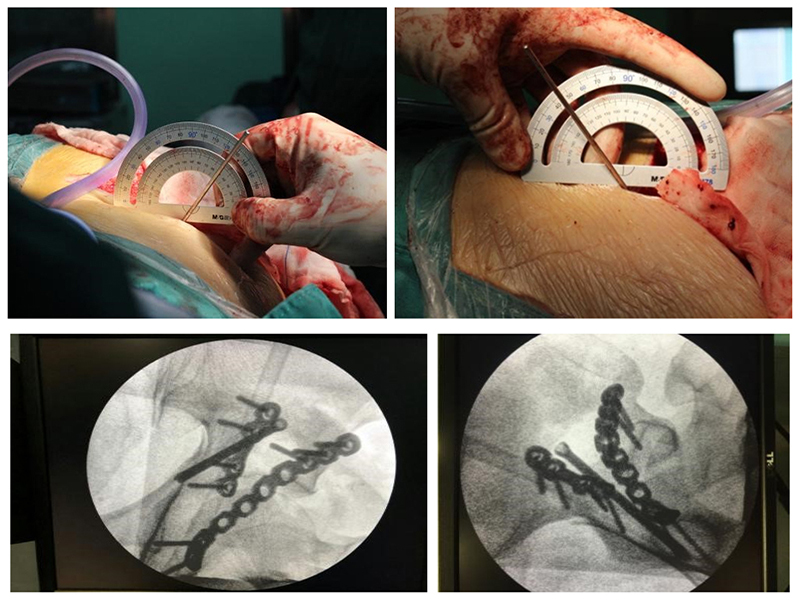

(1).jpg)

•

• ( )